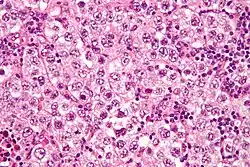

Micrograph of a seminoma, a common germ cell tumor.

Germinoma (including dysgerminoma and seminoma) 40–50 Malignant Sheets of uniform polygonal cells with cleared cytoplasm; lymphocytes in the stroma About 10% have elevated hCG